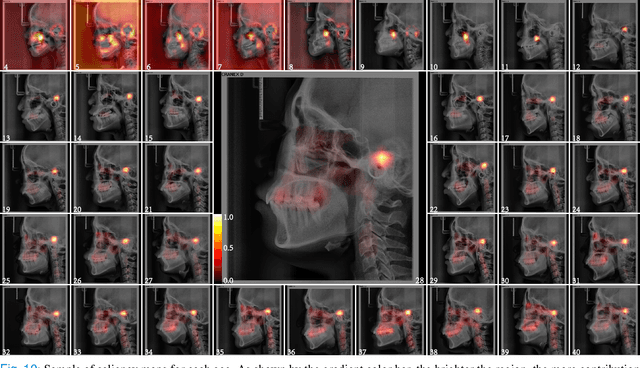

The traditional manual age estimation method is crucial labor based on many kinds of the X-Ray image. Some current studies have shown that lateral cephalometric(LC) images can be used to estimate age. However, these methods are based on manually measuring some image features and making age estimates based on experience or scoring. Therefore, these methods are time-consuming and labor-intensive, and the effect will be affected by subjective opinions. In this work, we propose a saliency map-enhanced age estimation method, which can automatically perform age estimation based on LC images. Meanwhile, it can also show the importance of each region in the image for age estimation, which undoubtedly increases the method's Interpretability. Our method was tested on 3014 LC images from 4 to 40 years old. The MEA of the experimental result is 1.250, which is less than the result of the state-of-the-art benchmark because it performs significantly better in the age group with fewer data. Besides, our model is trained in each area with a high contribution to age estimation in LC images, so the effect of these different areas on the age estimation task was verified. Consequently, we conclude that the proposed saliency map enhancements chronological age estimation method of lateral cephalometric radiographs can work well in chronological age estimation task, especially when the amount of data is small. Besides, compared with traditional deep learning, our method is also interpretable.